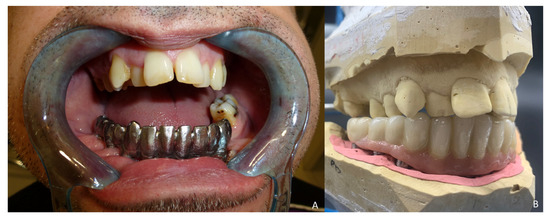

Six months later, the ossification of the graft and volume of the soft tissue were verified. An intraoral approach was performed, the titanium mesh was removed and the increase in height and width achieved with the graft was verified, showing the space beneath the titanium mesh completely filled with new hard tissue (Figure 8A). Seven dental implants were placed (Ticare®, Valladolid, Spain) (Figure 8B), and, four months later, the second surgical procedure of the implants was performed (Figure 9A). Evaluation of the occlusal vertical dimension and record centric relation was accomplished (Figure 9B) and the metal framework was evaluated intraorally (Figure 10A).

Figure 9. Prosthetic rehabilitation. (A) Second-stage surgical procedure and impression copings for dental rehabilitation with successful soft-tissue reconstruction. (B) Evaluation of the occlusal vertical dimension and record centric relation.

Figure 10. Implant prosthesis. (A) Metal framework evaluated intraorally. (B) Functional rehabilitation with a ceramic fixed implant-supported prosthesis.